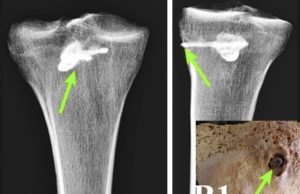

Çalışmanın en çarpıcı bulgularından biri, günümüz doğu Gürcistan’ında yer alan İberya (Kartli) Krallığına ait erken Orta Çağ bireylerinde görülen bilinçli kafatası şekillendirme uygulamasına ilişkin. Bu kültürel pratiğin uzun süre Orta Avrasya Bozkır topluluklarına özgü olduğu düşünülüyordu.

“Genetik olarak Orta Asyalı olan ve kafatası şekillendirilmiş çok sayıda birey tespit ettik; hatta Avarlar ve Hunlarla doğrudan soy bağları bulduk” diyor başyazar ve genetikçi Eirini Skourtanioti.

Ancak analizlerimiz, bu bireylerin çoğunun göçmen değil, yerel olduğunu gösterdi. Bu, büyük olasılıkla göçebe gruplar tarafından bölgeye yayılan bir pratiğin kültürel olarak benimsenmesine güçlü bir örnek.”

Çalışmanın ortak yazarlarından, Tiflis Devlet Üniversitesi Antropolojik Araştırmalar Laboratuvarı başkanı Liana Bitadze, bulgunun önemini doğruluyor: “Daha önce bu soruyu karşılaştırmalı morfometrik analizlerle ele almıştık. Şimdi ise antik DNA analizi tamamen yeni bir kanıt hattı sunarak daha kesin yanıtlara ulaşmamıza yardımcı oluyor.”